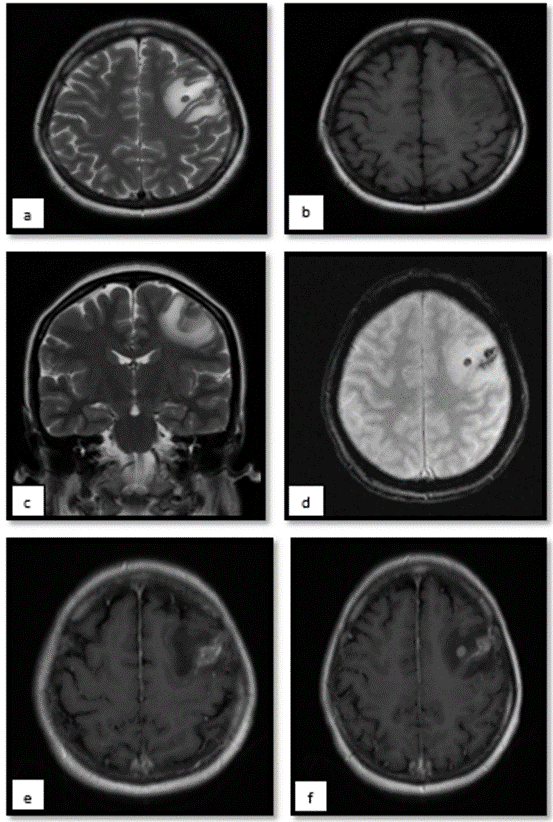

Magnetic resonance imaging of the brain was performed (Figure 2)with evidence of an intra-axial lesion in the deep white matter of the left frontal lobe measuring 5 mm, oval, with peripheral contrast enhancement, which is associated with extensive vasogenic edema (thickness up to 12 mm). and in ferromagnetic sequences, bleeding within the lesion is evident. Without ruling out neuroinfection, paraclinical tests are performed, with a complete blood count showing anemia and mild hypokalemia, as well as metabolic acidosis partially compensated with mild oxygenation disorder. Lumbar puncture without signs of an infectious process, however, with a report  of elevated hCG in CSF (Table 2). Chest tomography (Figure 3) with evidence of bilateral pleural effusion predominantly on the right. Numerous nodules with soft tissue density are identified in the right hemithorax. The largest of them projected in the posterior segment of the basal lobe with a long axis diameter of 68 mm. In the left hemithorax, nodules with the same characteristics were identified, the largest of which was projected in the anterior segment of the apical lobe with a long axis diameter of 12 mm.

occrs-molar

Figure 2. Magnetic resonance imaging of the brain showing intra axial lesion in the deep white matter of the left frontal lobe that measures 5 mm, oval, isointense on T1 (B), hypointense on T2 (AC), which is associated with extensive vasogenic edema (thickness up to 12 mm). and in ferromagnetic sequences, bleeding within the lesion is evident, characteristic of these. With peripheral contrast enhancement (F).

There are few documented cases of brain metastases due to choriocarcinoma, however, 10-20% of cases have been described. They are highly vascularized tumors and have a propensity to bleed as well as their metastases. The blood products present may be evident on MRI as loss of signal and “blooming” or flowering on T2* and intrinsically hyperintense signal on T1 [9]. They metastasize hematogenously with the possibility of presentation with aneurysmal lesions and other subdural or intraparenchymal hematomas [10].